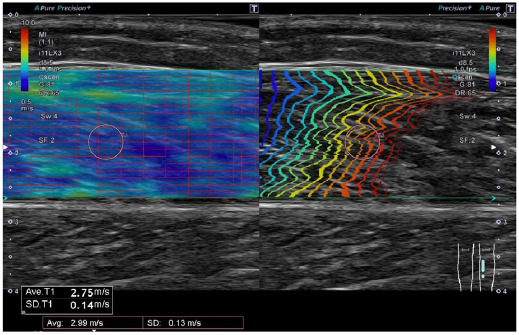

Methods: Eighteen healthy young participants were enrolled in this study. DS with one set (DS1) or four sets (DS4) of 30 s each was performed randomly. Shear wave velocity in the medial gastrocnemius (MG) was measured before and after DS to assess muscle stiffness of the MG.

Results: Two-way repeated-measures analysis of variance (condition × time) showed a significant interaction with the shear wave velocity (p = 0.02). Shear wave velocity significantly decreased after the DS4 than before (before:3.09 ± 0.59 m/s; after: 2.86 ± 0.43 m/s). However, no significant differences were observed in shear wave velocity between before and after DS1 (before: 2.96 ± 0.56 m/s; after: 3.19 ± 0.56 m/s). There were no significant differences in shear wave velocity at baseline condition. After the intervention, significantly lower shear wave velocity was observed in DS4 than in DS1.